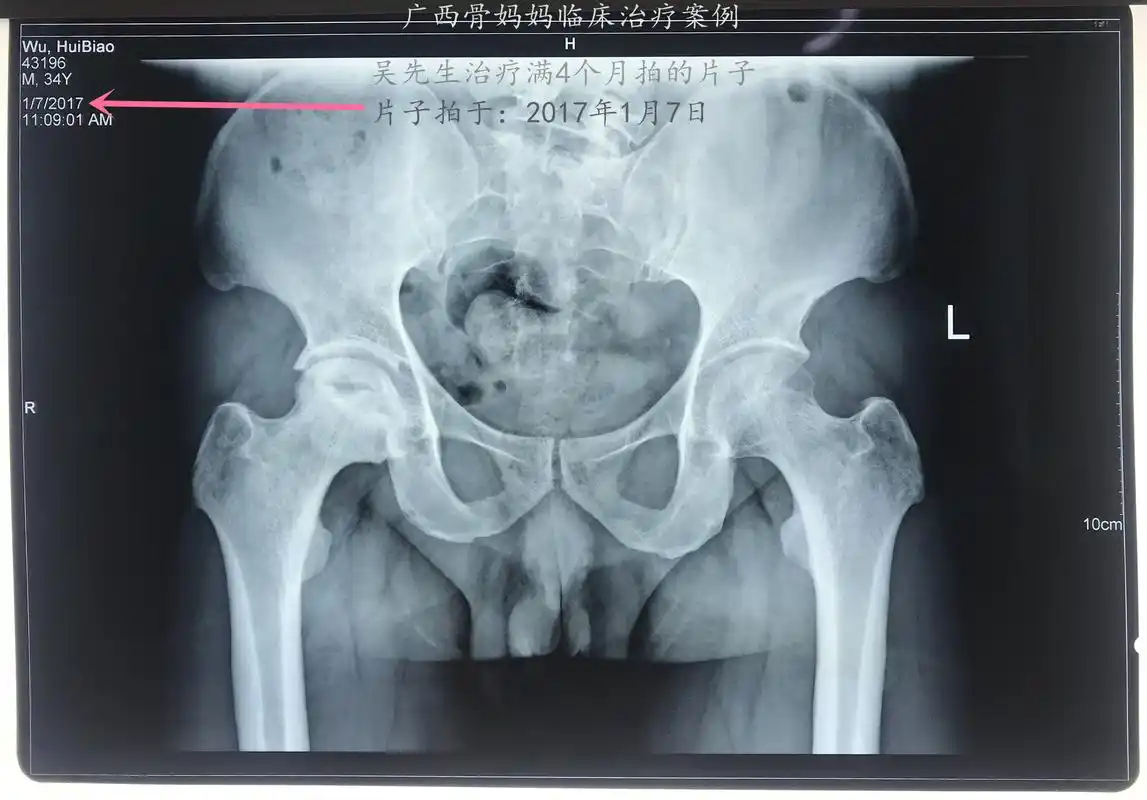

股骨头坏死中医成功案例分享:这个患者治疗全程x线片的变化亮眼